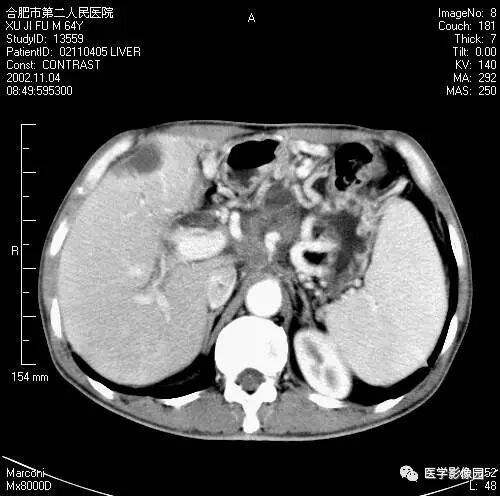

图6-4-13胰腺癌

CT平扫见胰体、尾部局限性肿大,

其内境界不清的低密度灶(↑);

肝右叶有多个低密度转移灶(长↑),

并见腹水